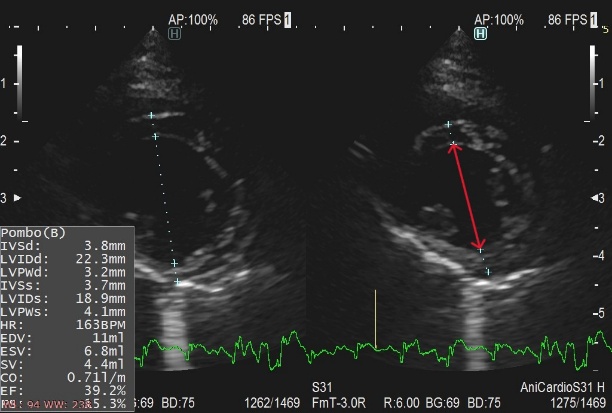

猫の心疾患の多くは肥大型心筋症です。その他、拘束型や拡張型と呼ばれる心筋症も存在します。稀ですが先天性の心疾患(心房中隔欠損症など)が認められるケースもあります。

肥大型心筋症は、左心室の筋肉が過剰に分厚くなってしまい、心臓がうまく動けなくなってしまう病気です。原因のほとんどは遺伝であり、アメリカン・ショートヘアやメイン・クーンで多いといわれていますが、すべての猫で発症する可能性があります。発症の年齢も若齢から高齢まで様々です。

また、血液の渋滞によって肺に水が溜まる肺水腫や、肺の外に水が溜まる胸水症を伴っていることも多く、呼吸困難に陥ってしまいます。